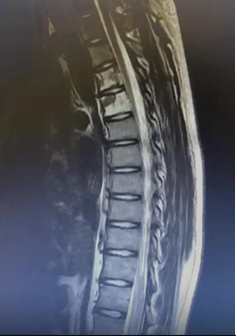

Based on this diagnostic suspiicion, a lumbar puncture was performed, which showed the foUowing results: 240 cells x mm3, 100% mononuclear predominance, protein 164.5 mg/dl, gllucose 2 mg/dl, with gram negative stain, acid fast bacilli negative and negative chinese Ink, a panel of PCRs for viral, bacterial, fungal and parasitic meningitis was performed, which was negative, and cernbrospinal fluid was sent for cytology for pathollogy. Whiile waiting for the result of the pathology, we performed magnetic resonance imaging of the simple neuroaxis (Figure 1) and contrast with which we demonstrated images suggestive of neurolymphomatosis of the cervical plexus and at the level of the cauda equina, the C4 and C5 vertebral bodies with heterogeneous siignal intensity of the bone marrow involving both pedicles with heterogeneous enhancement to the administration of contrast with gadolinium, T11 vertebral body to the administration of contrast with gadolinium presents sliight enhancement homogeneous, both kidneys with increased volume, with lobulated edges and heterogeneous parenchyma due to multiplle wedge-shaped lesions with an infiltrative appearance, which after the administration of contrast present heterogeneous reinforcement, iincireased spleen volume with a maximum longitudinal diameter of 13.5 cm.

Figure 1 Simple MRI and neuroaxis, lateral view.